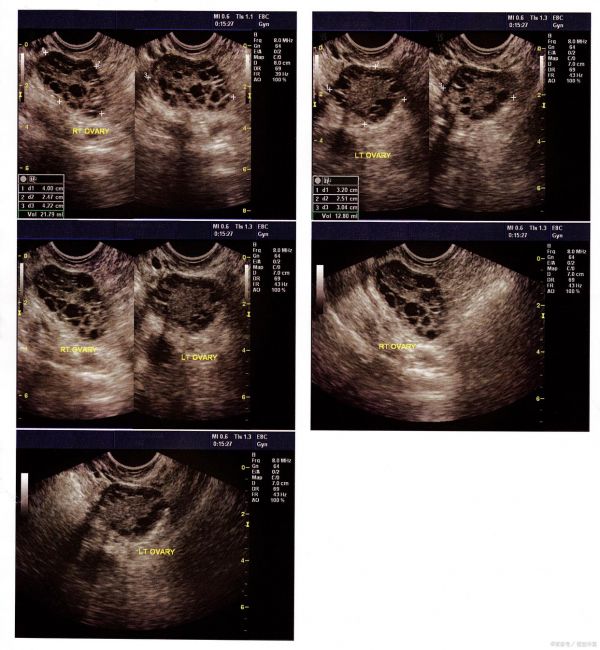

在备孕的道路上,多囊卵巢综合症(简称“多囊”)无疑是许多女性心中的一道坎。一提到多囊,不少女性都会闻之色变,因为它常常与“难怀孕”这个词紧密相连。确实,多囊患者在求医过程中,最常听到的建议就是:要减肥、要运动、要合理饮食。没错,除了药物控制,饮食调控对于多囊患者来说至关重要。